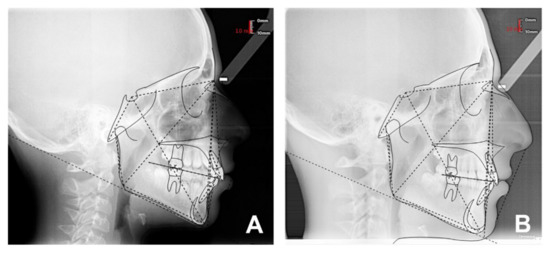

| Sagittal plane analysis: SNA (angle comprised between Sella–Nasion and Nasion point A segments) SNB (angle comprised between Sella–Nasion and Nasion point B segments) ANB (angle comprised between Nasion point A and Nasion point B segments) Vertical plane analysis: Sna-Snp^Go-Gn (intermaxillary angle, angle comprised between the bispinal plane and the mandibular plane) S-N^Go-Gn (mandibular angle, angle comprised between the Sella–Nasion segment and the mandibular plane) PFH/AFH (posterior facial height and anterior facial height ratio) Growth predictors: N-S-Ar (saddle angle comprised between Nasion–Sella and Sella–Articular segments) S-Ar-Go (articular angle comprised between Sella–Articular and Articular–Gonion segments) Ar-Go-Me (gonial angle comprised between Articular–Gonion and Gonion–Menton segments) Ar-Go-N (upper gonial angle comprised between Articular–Gonion and Gonion–Nasion segments) N-Go-Me (lower gonial angle comprised between Nasion–Gonion and Gonion–Menton) Dental analysis: Is:NA (maxillary incisor distance) Ii:NB (mandibular incisor distance) OVJ (overjet) OVB (overbite) IsIi: interincisal angle (angle between the major axis of the upper and lower incisors). Upper airway space analysis: SPAS: superior posterior airway space (distance between the soft palate and the posterior wall of the nasopharynx measured along a line parallel to Gonion–Menton (Go–Me) plane) MAS: medium airway space (distance between the lower tip of the soft palate and the posterior wall of the oropharynx measured on a line parallel to Go–Me plane) IAS Inferior Airway Space (distance between the lingual base along the mandibular Go-Me plane and the posterior wall of the pharynx) Mandible measurements Ar-Go (ramus height measured on Articular-Gonion segment) Go-Me (corpus length measured on Gonion-Menton) |